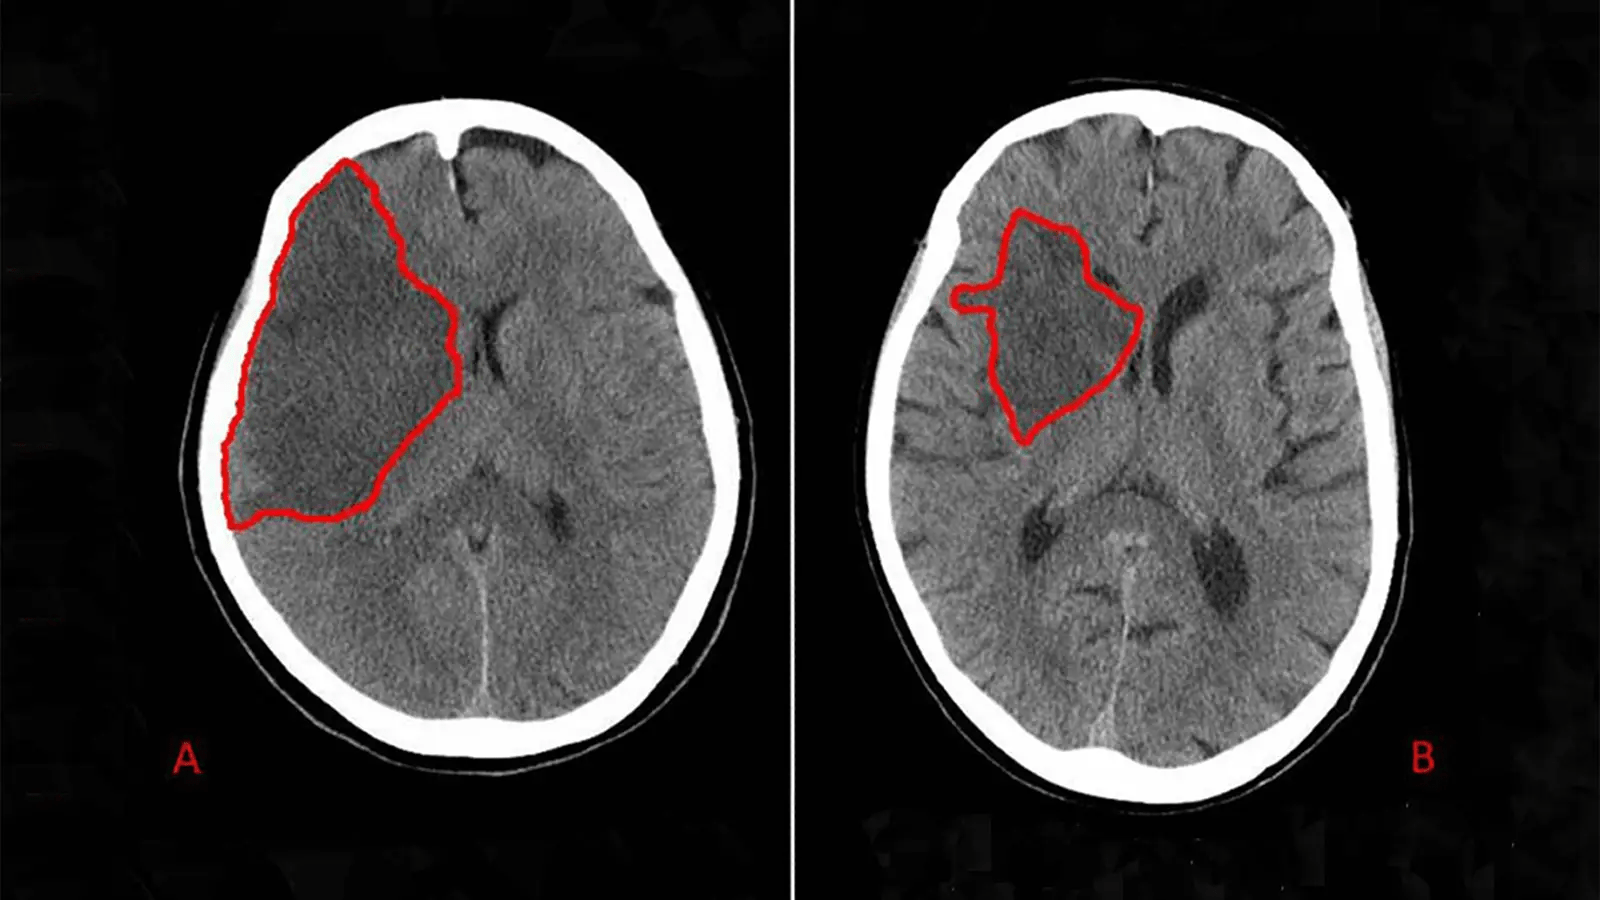

Badania wskazują, że migotanie przedsionków powoduje tworzenie się skrzepów w górnych komorach serca.

Te skrzepy mogą się odłączyć, blokując przepływ krwi do mózgu. Ale kolejne odkrycie zaskakuje najbardziej.

Badania wykazują, że migotanie przedsionków może znacznie zwiększać ryzyko udaru w porównaniu z osobami o prawidłowym rytmie.